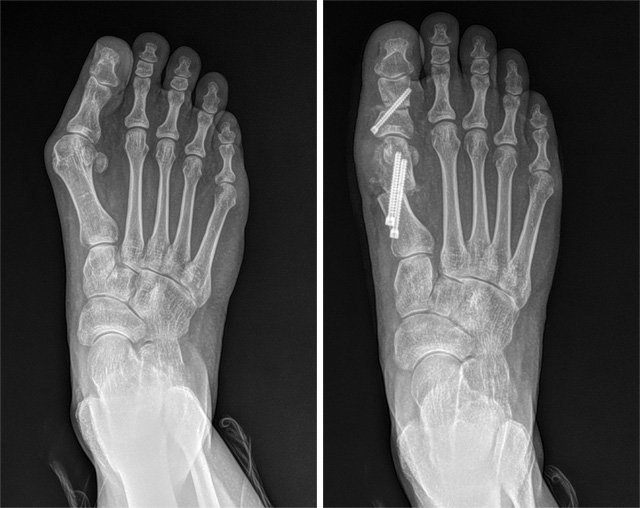

최소침습 무지외반증 수술 전(왼쪽)과 후의 발 X선 사진. SNU서울병원 제공

최근에는 절개를 최소화하는 ‘최소 침습’ 수술이 대세다. 흉터가 작고 통증이 크지 않은 게 장점이다. 서 원장의 경우 엄지발가락 옆쪽에 2mm 크기의 구멍 3개를 뚫는다. 절개 범위가 기존 수술법의 20분의 1 크기다. 이 구멍으로 도구를 집어넣어 실시간 엑스레이 화면을 보면서 뼈를 깎는다. 골막을 건드리지도 않는다. 마지막으로 핀으로 고정하면 수술이 끝난다. 수술에 걸리는 시간은 20분 남짓. 바로 이 수술 기법을 부산의 A 의사가 배우고 간 것이다.